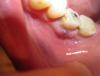

happy_mam Опубликовано 10 июля, 2013 Поделиться Опубликовано 10 июля, 2013 Добрый вечер!В понедельник (08.07) поставили штифт на леченый, на сломаный зуб (правая 6), с дальнейшим прицелом убрать его под коронку.От зуба, на момент прихода к врачу, осталась одна стенка (к щеке) и корешки ранее залеченые.Недели за 2 до прихода в течении одного дня наблюдала ноющую боль под этим зубом с чуствительной болевой точкой вне полости рта, а снаружи под челюстью и в районе уха, где по моим представлениям соединяются верхняя и нижняя челюсть, вобщем пополоскала день травой и все успокоилось, я посчитала, что просто надула, т.к. в машине ежу с открытым окном.1. После установки штифта, через пару часов стало больно накусывать и ощутила дискомфорт, раствор, которым восстанавливали зуб залез слегка на 5-ку и 7-ку, зубу стало тесновато.2. И утром я снова была у врача. Мне сняли лишнее с зуба, вкололи обезболивающее и какое-то лекарство от воспаления. Но даже под анастезией зуб был чувствительным, не то что при накусывании, а даже и при касании языком.Начала принимать Ципролет 500 и полоскать Календулой и Хлоргексидином, а чтобы не дергало и не так ныло еще и Нурофеном запила.К вечеру второго дня возникла припухлость в районе нижней челюсти, но не в полости рта, а снаружи, которая и до сих пор наблюдается и слегка выросла имея в диаметре около 4 см, а на ощупь представляет собой некоторое округлое уплотнение.3. Сегодня утром пришла к доктору, сделали рентген, сходили к хирургу, он сказал, что не видит смысла резать - надо лечить. И мне снова сделали обезболивание и укол лекарством за 10 руб. ампула (я спросила у доктора, она подтвердила, что это антибиотик) и наначили пить Ципролет 5 дней и полоскание.Надо признать, что боль чутка стихла, я могу смыкать челюсть без резкой боли (но тупая боль еще есть ) и безболезненно трогать зуб языком. НО!!! на десне у корня возник небольшой мешочек, который я тут же и тыркнула пальцем, внутри что-то лопнуло, стало жутко больно, я прополоскала рот и снова надавила на мешочек совсем слегка, он резко лопнул и вышел гной и кровь, я полоскала все обильно хлоргескидином и календулой. Немного покровоточило и перестало. Зубу стало как будто бы легче, но может это воздействие половинки Нурофена (я уже ничего не понимаю).Меня волнует припухлость на щеке и вообще дальнейшая жинь моего многострадального зуба.Подскажите, пожалуйста, все ли правильно установлено и верное ли лечение назначено.Я первый раз у этого врача, да и вообще в Абхазии впервые делаю зубы Рентген до; после; и Фото "внутри" и "снаружи": Ссылка на комментарий